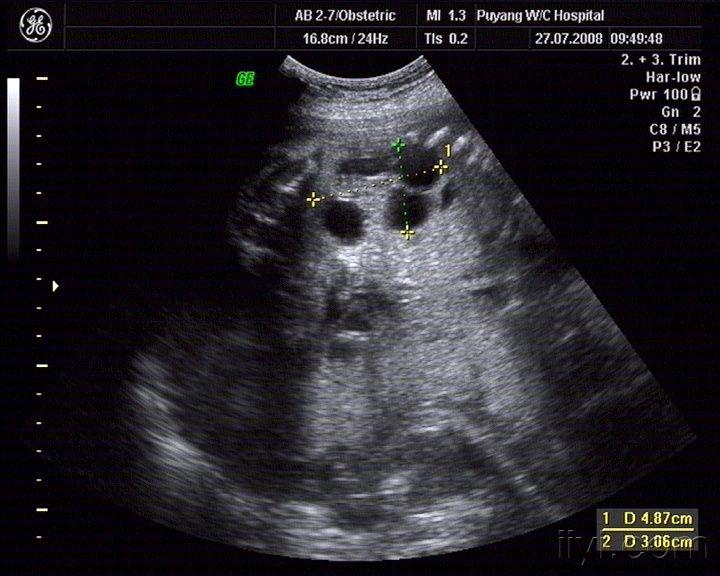

胎儿多囊肾?

图片尺寸768x576